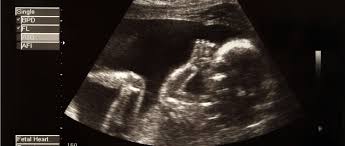

Et puis, il y a quand même un "hic", avec l’IVG, un tout petit "hic", de quelques centimètres : si vous avez le bonheur d’assister à l’échographie d’un fœtus d’à peine quelques semaines, vous verrez un petit d’humain parfaitement constitué et vivant, qui bouge et réagit à l’environnement de sa mère. L’avortement d’un fœtus de 12 semaines (14 semaines aujourd’hui), et même de nettement moins, c’est l’interruption d’une vie en cours, et pas seulement en devenir. Cela, c’est un fait, ce n’est pas une opinion, ni une polémique. L’IVG, n’en déplaise à ses défenseurs, n’est pas une conquête de la Femme. C’est un constat d’échec, un drame humain.